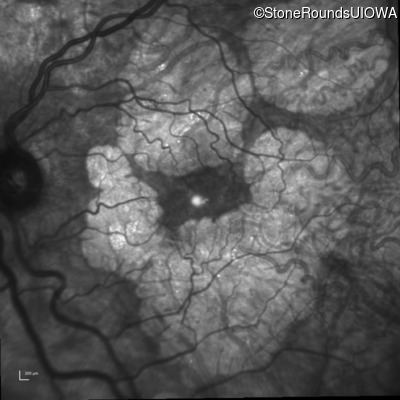

Age at visit: 51 years

OD OS

This 51 year old woman first experienced some abnormality in her distance vision when she was 27 years old. She feels that her vision has been stable since that time.

Diagnosis & molecular findings

Disease Gene Allele 1 variant(s) Allele 2 variant(s) Inheritance mode

AR Stargardt Disease ABCA4 Gly1507Arg GGG>AGG IVS42+1 G>A AR